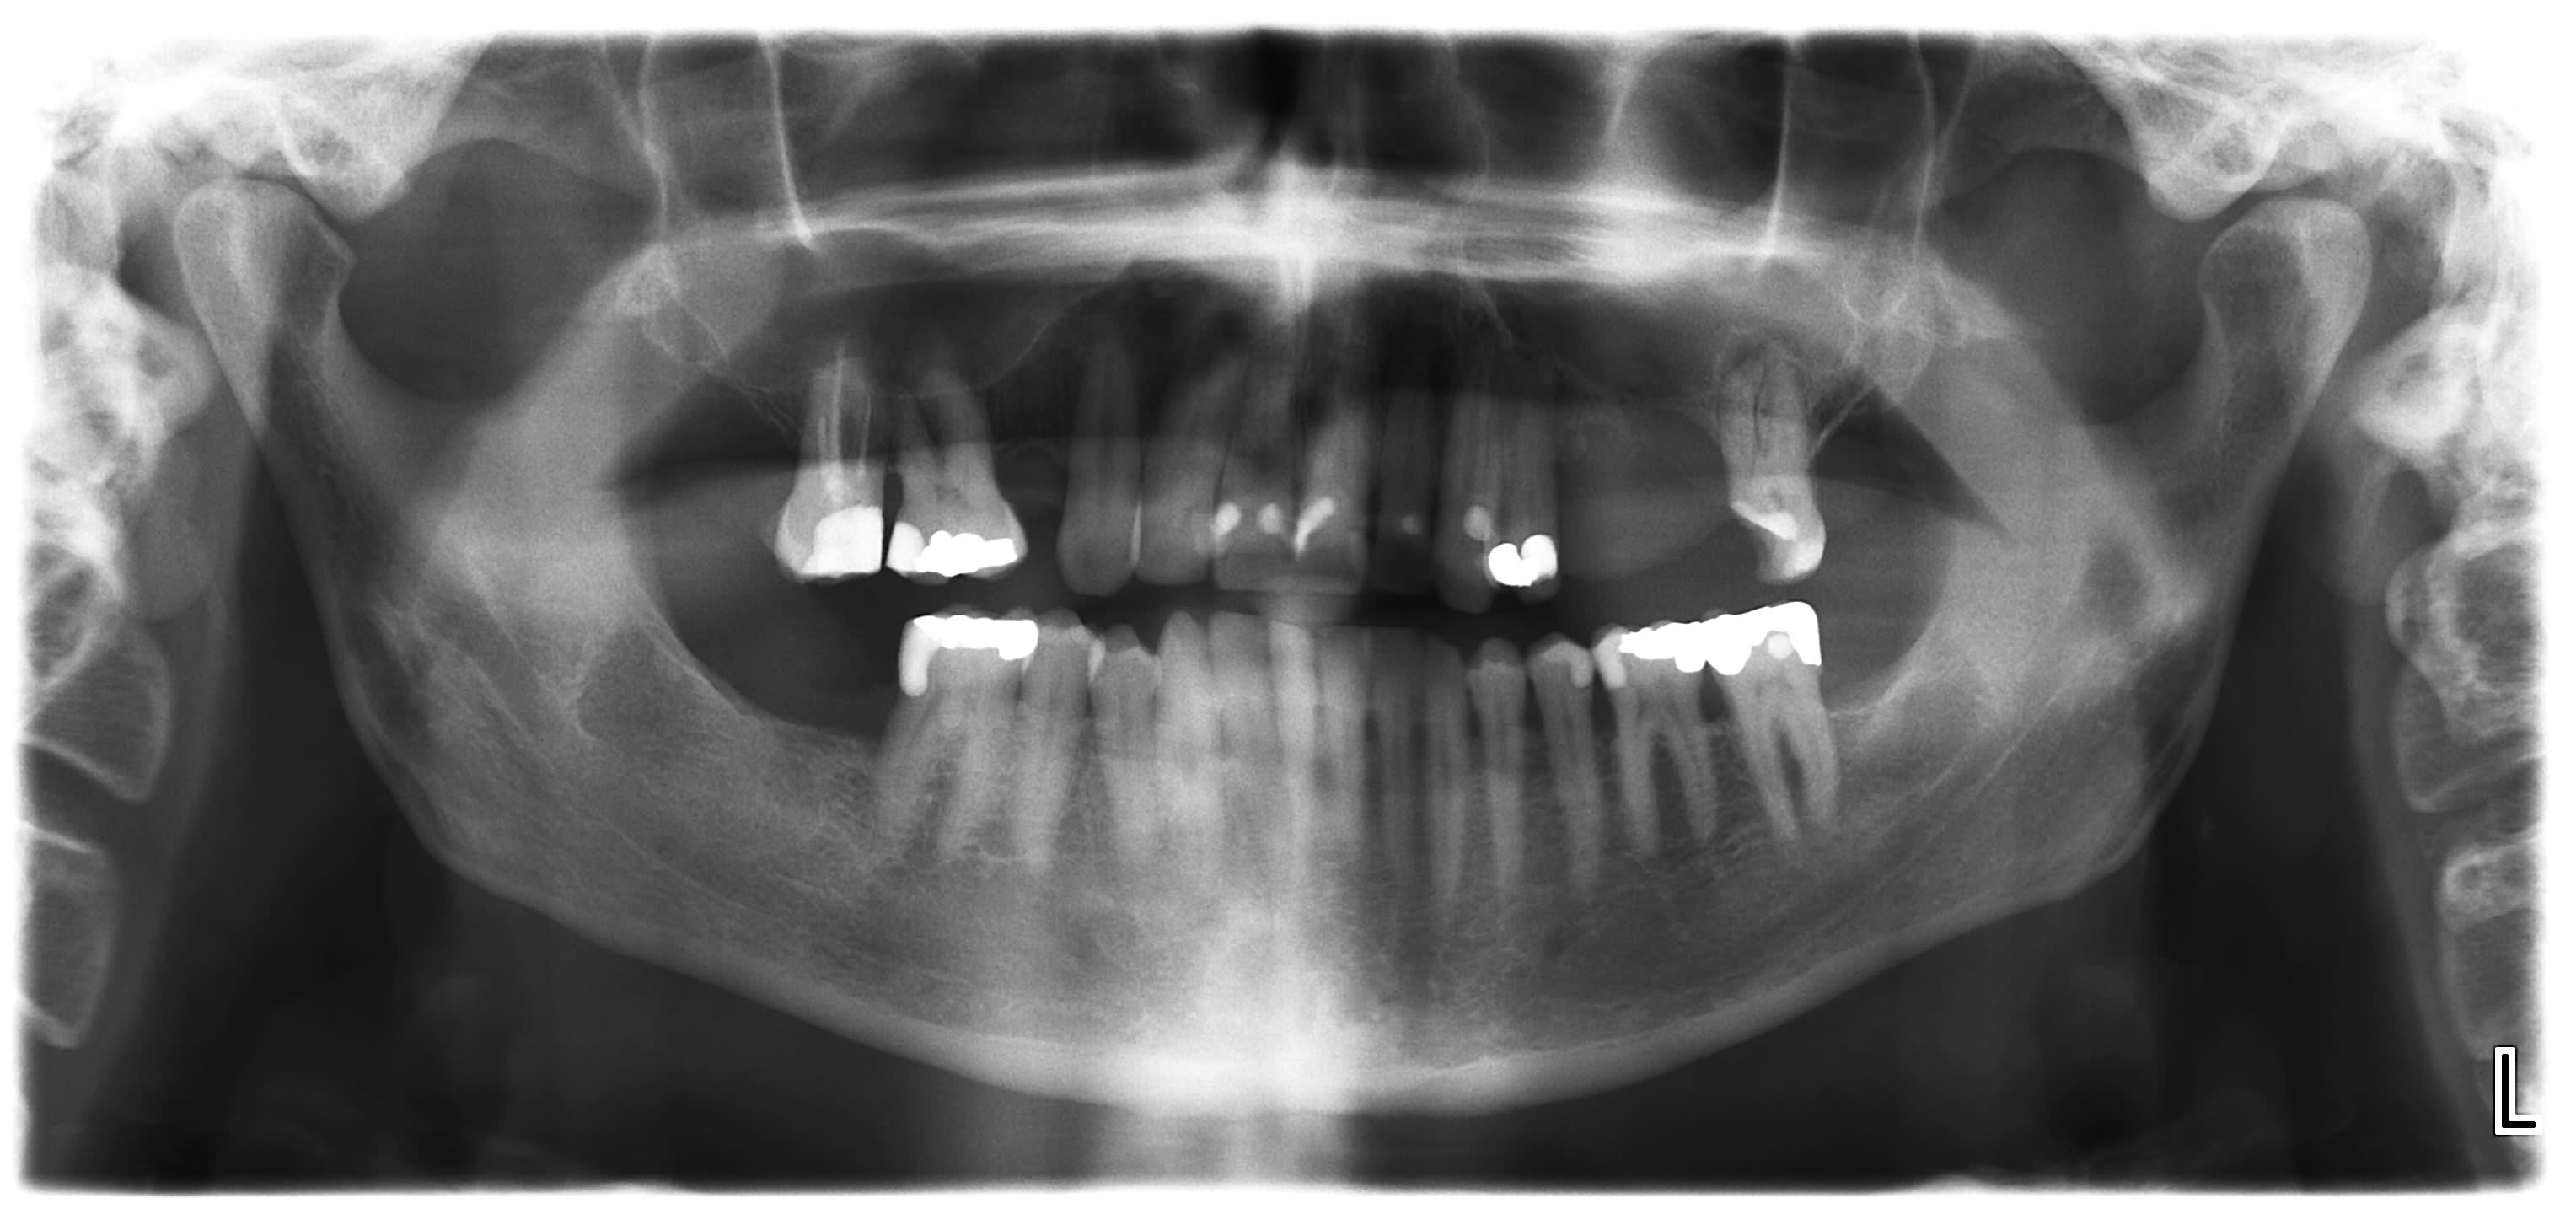

Juste pour info le CBCT qui demontre bien qu une PANO est une somme de projection, rotation etc...

Sur la coupe frontale on voit que la dent est au niveau du cornet inferieur de la paroi nasale et non derriere la cavite orbitaire :0)

En continuant avec les envahissements de sinus.

Une idee de diagnostic? Evolution depuis 3 mois, facilement mobilisable, saignement a palpation, qui a envahit le sinus.

Patient a aucune douleur. Pas d adenopathies peripheriques.

En bonus un autre probleme de sinus...